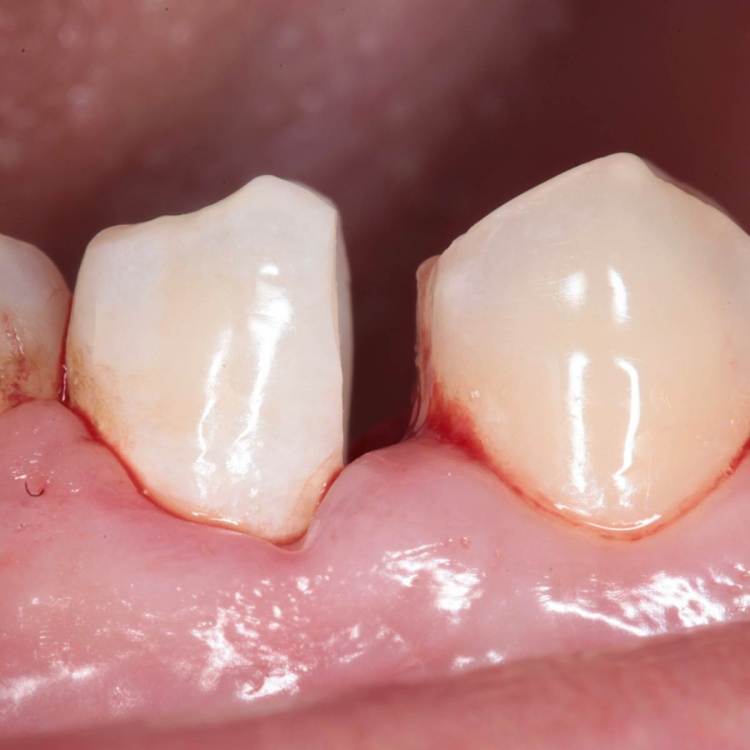

Как часто мы сталкиваемся с такими процессами и как редко пациент сам предъявляет какие то жалобы на такие зубы. Максимум это… застревание пищи.

Глубина полости ниже уровня десневого края на 2-3 мм. Коагуляция, ENDO, анатомичный билдап, проверка качества реставрации и отсутсвие нависающего края (интерпроксимальный снимок), рекомендации.